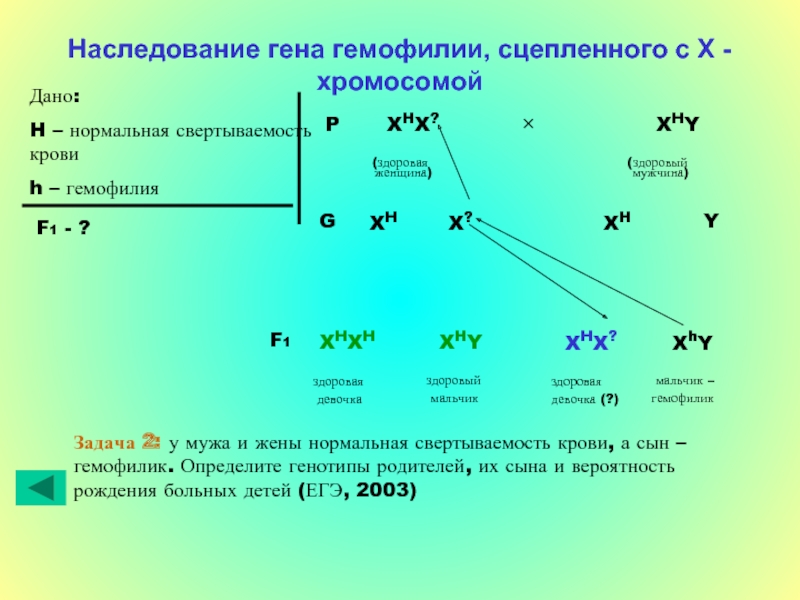

Генетика гемофилии: рецессивные гены и их проявления